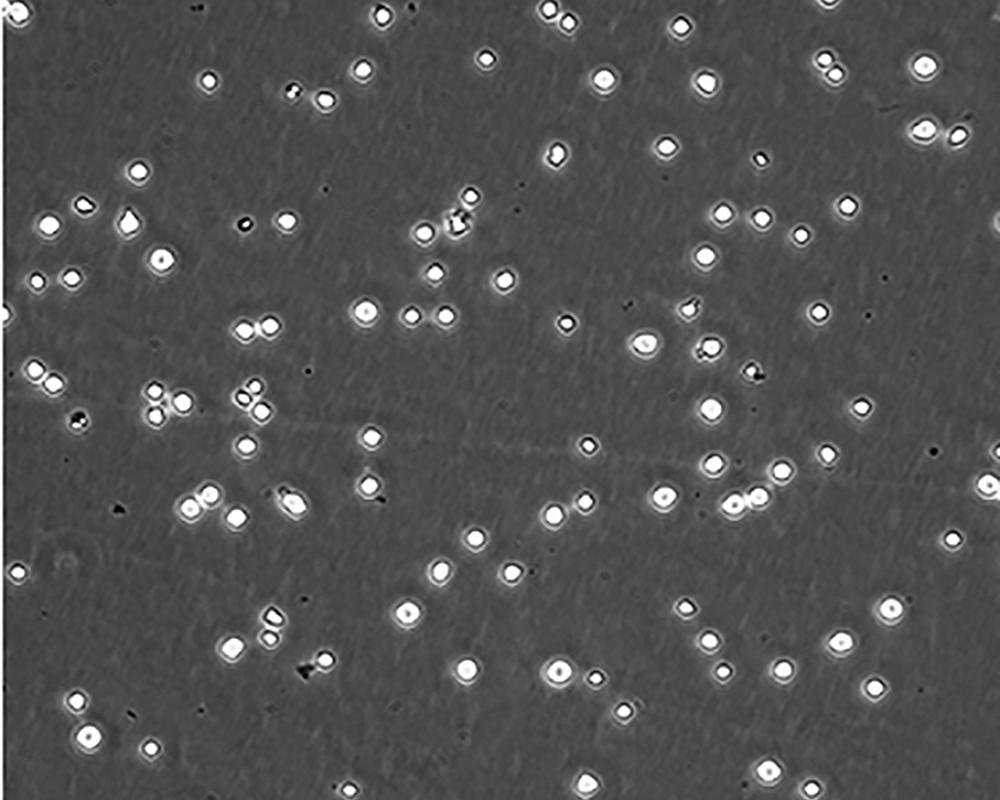

生長(zhǎng)特性 suspension

形態(tài)特征 lymphoblast

細(xì)胞描述 CEM/C1是人T細(xì)胞白血病細(xì)胞株CCRF-CEM(見(jiàn)ATCC CCL-119)具有喜樹(shù)堿抗性的衍生株。1991年細(xì)胞株選擇并亞克隆了對(duì)CPT的抗性。細(xì)胞表現(xiàn)出對(duì)CPT類似物水溶性的托泊替康和非水溶性的9-氨基-CPT及10,11-亞甲二氧基-CPT具有交叉抗性。CEM/C1細(xì)胞對(duì)CPT的敏感性較母系CEM細(xì)胞低31倍。CEM/C1細(xì)胞表現(xiàn)非典型的多藥抗性和轉(zhuǎn)換拓補(bǔ)異構(gòu)酶I催化活性。對(duì)CPT的抗性維持6個(gè)月以上。